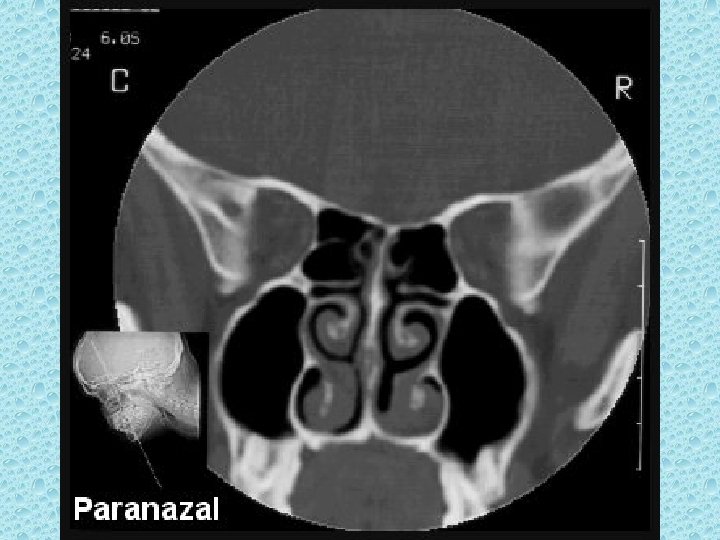

PARANAZAL SİNÜSLER • • Maksiller (2) Frontal Etmoid Sfenoid

NAZAL BOŞLUKTAKİ YAPILAR • • Konkalar: alt, orta, üst Meatüsler: Alt, orta, üst Nazal septum Koana

OSTEOMEATAL ÜNİTE • • Orta meatüs Unsinat proçes Hiatus semilunaris İnfindibulum